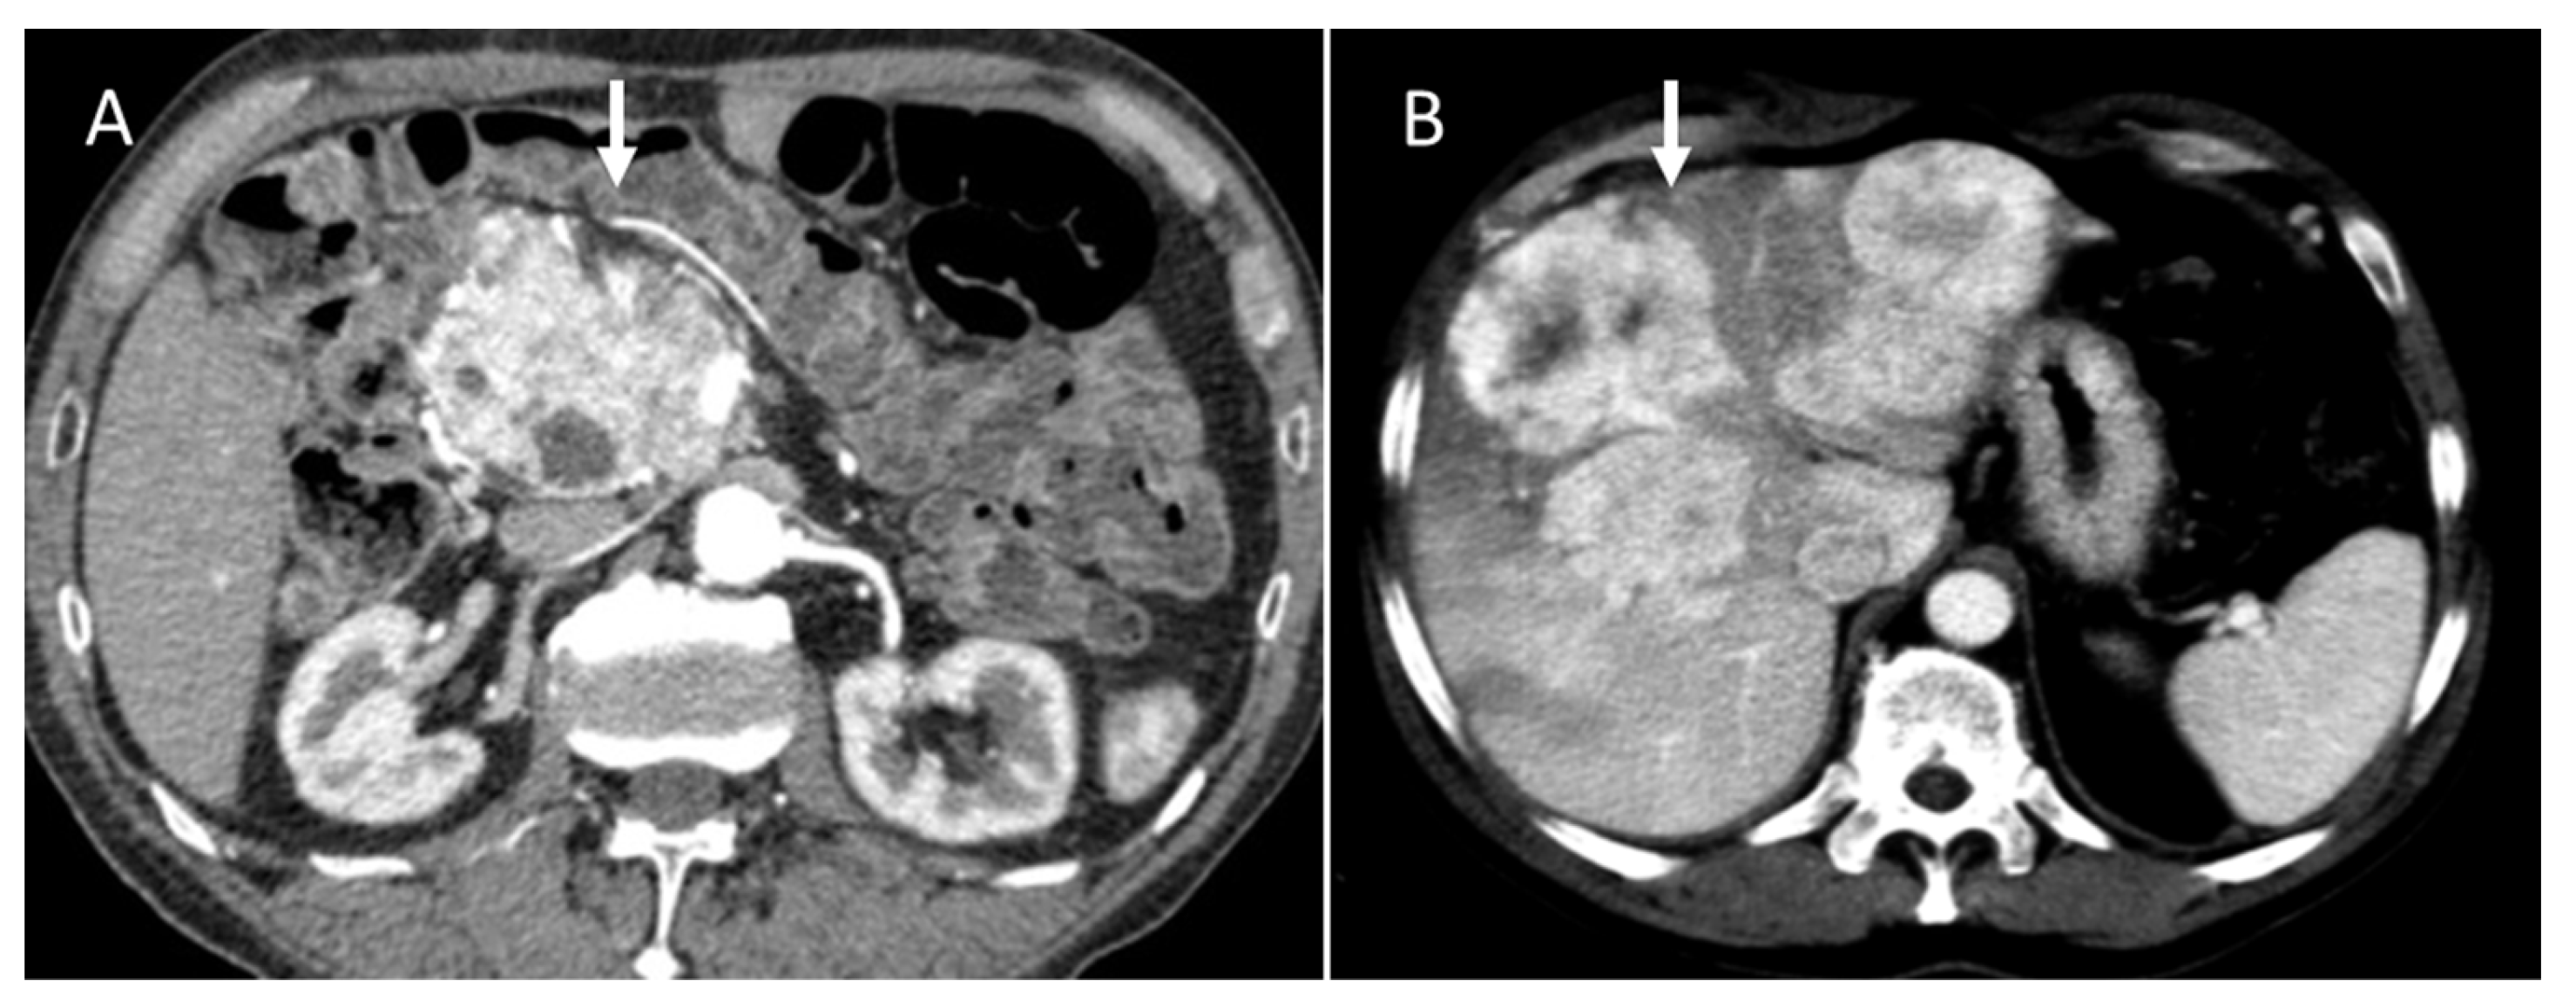

Figure 1.

Portal CT evaluation of small bowel NEN (arrow in (A)): intraluminal enhanced polypoid lesion (arrow) with desmoplastic reaction (arrow in (B)).